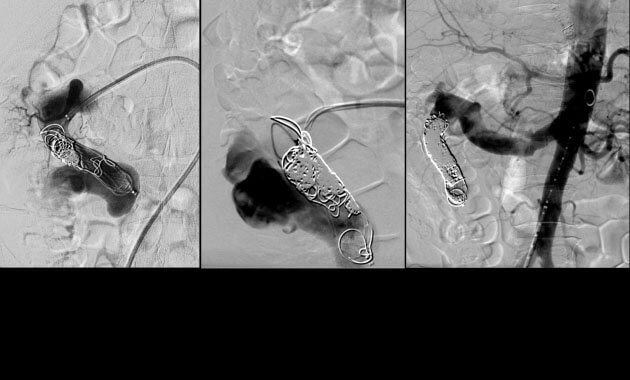

Men’s Health

- Conditions: Benign prostatic hyperplasia (BPH), varicocele

- Services: Prostate artery embolization (PAE), varicocele embolization, varicoceles male infertility treatment